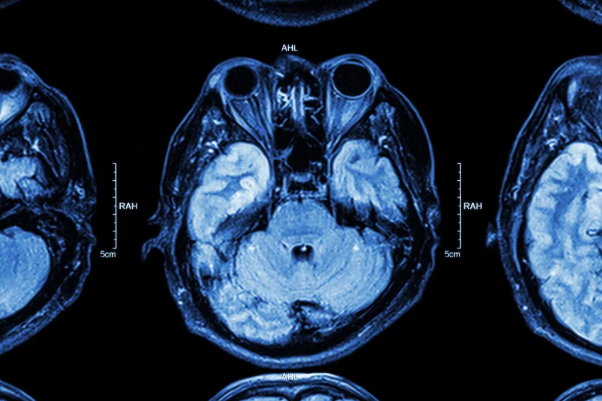

Chuyên gia Augustin Lecler, phó giáo sư tại Đại học Paris, Pháp cho biết, nghiên cứu bao gồm 129 bệnh nhân Covid-19 nhập viện cho thấy thông qua thông tin chụp cộng hưởng từ não, trong đó 9 người (7%) có nốt sần ở mắt, và 8 người có nốt sần ở cả hai mắt.

Các nhà nghiên cứu đang theo dõi 9 bệnh nhân có bất thường về mắt này, và cũng đang nghiên cứu những bệnh nhân bị bệnh nặng khác bằng phương pháp chụp cộng hưởng từ và khám mắt toàn diện.